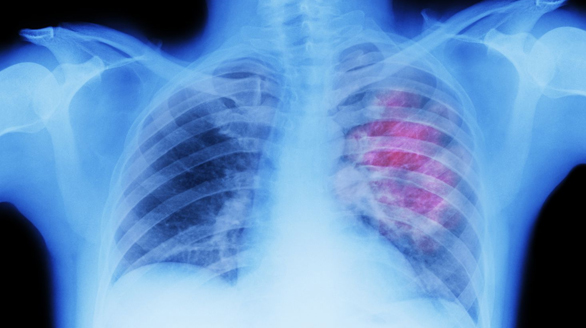

Pediatric Thoracic Surgery

Kidsurg deals with surgical problems affecting the chest, whether congenital or acquired. Such problems include but not limited to

Tracheo-esophageal Fistula

Congenital Lung Malformations

Bronchogenic/Foregut Duplication Cysts

Mediastinal and Lung Tumors

Stricture Esophagus

Chest Wall Lesions

Hydatid Disease of Lung

Empyema Thoracis